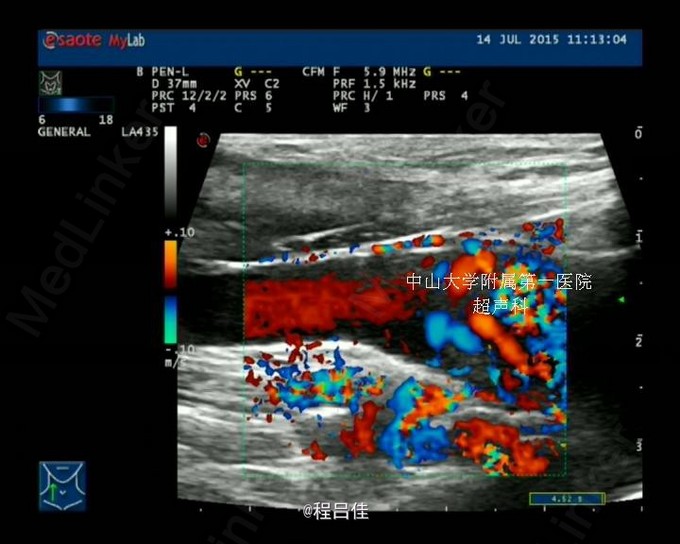

查体: 1.T37℃, P90次/分,R20次/分,BP120/80mmHg。颈软,外形对称,未见颈静脉怒张,未见血管搏动,气管偏左。右侧甲状腺II度肿大,内扪及数个结节,质硬,边界不清,无压痛,随吞咽上下移动。左侧(-)。颈部淋巴结未扪及。突眼征(-),双手震颤试验(-)。 辅查: 甲工5项正常、肺肿瘤组合(-)、血清降钙素原PCT1.31 ng/mL ↑ 、术后钙Ca 1.83 mmol/L ↓ 2.甲状腺US: 右叶甲状腺CA,向胸骨后延伸并侵犯右侧颈静脉起始段;左叶甲状腺滤泡囊肿。 双侧颈部未见异常肿大淋巴结。 3.胸片: 右上纵隔增宽,气管受压向左侧移位 4.心脏彩超:二尖瓣前叶脱垂并关闭不全(轻微),右房近上腔静脉入口处团块状回声。 5.PET-CT:甲状腺右叶及峡部肿块(向下延伸至胸骨上缘水平,邻近气管受压),代谢活跃,考虑恶性肿瘤,右侧颈内及购买起始段、右头臂静脉、上腔静脉、右心房上部节段性代谢增高,考虑癌栓形成。甲状腺左叶小结节,代谢未见异常,考虑结节性甲状腺肿或小囊肿。 6.术中冰冻快速切片报告: (左侧甲状腺)送检3.5x2.5x2cm暗红组织一块,切面暗红,无明显结节。冰冻快速切片报告镜下:结节性甲状腺肿,未见肿瘤。

诊断:1.双侧甲状腺肿物:右侧甲状腺滤泡状癌。2.胸骨后甲状腺肿物,甲状腺癌侵犯颈静脉。 处理:完善术前检查,全麻下行“双侧甲状腺全切术+非体循下右颈内静脉、右心房癌栓切开取出术”,术中出血3000ml,术程顺利;术后患者终身口服优甲乐,定期监测血浆TSH和T4。